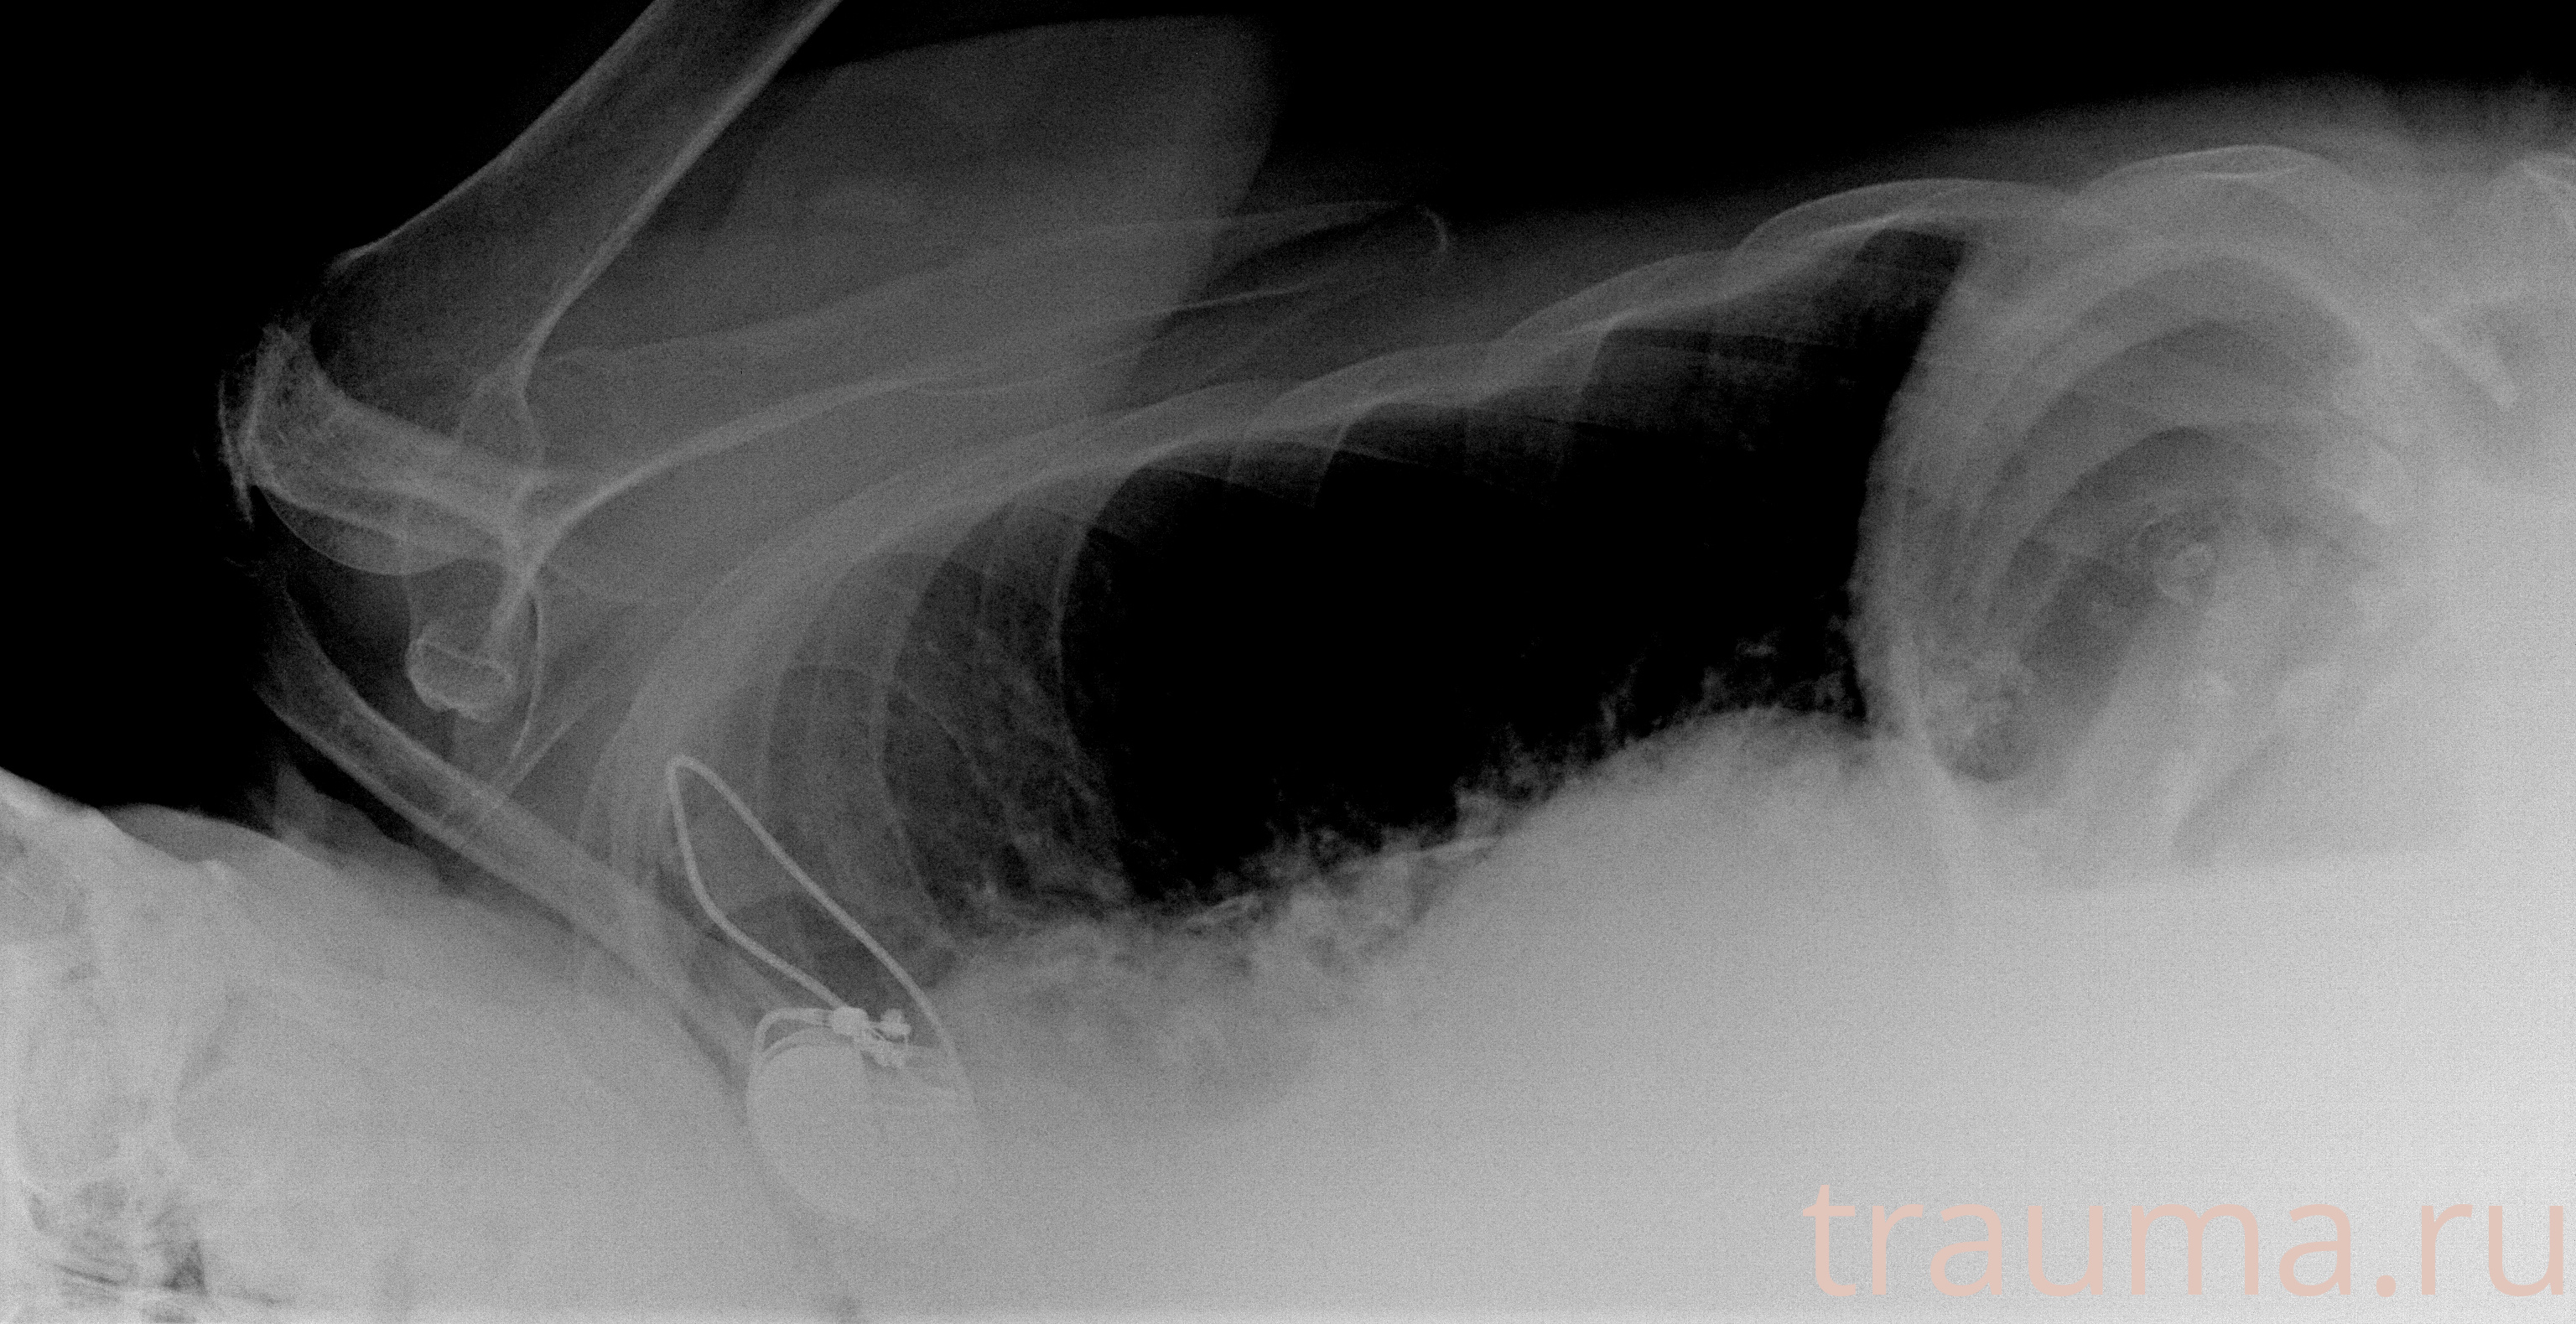

Рентгенограммы

Рентген на дому: по вашему адресу приезжает врач-рентгенолог, травматолог-ортопед с мобильным рентгеновским аппаратом, проводит диагностику травмы или заболевания, делает необходимые рентгенограммы, дает рекомендации по дальнейшему лечению. Получить качественные снимки в домашних условиях возможно благодаря уникальной методике, разработанной МосРентген Центром для института  Склифосовского